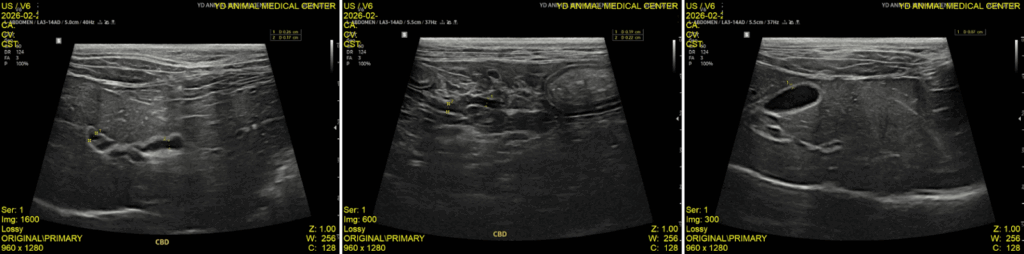

이후 추적 검사에서는 간 수치가 하락하였고, 초음파상 확장되어 있던 Cystic duct의 직경이 감소하였으며 담낭 확장도 줄어드는 양상이 확인되었습니다. 이에 따라 반응성이 양호하다고 판단하여 입원 치료에서 통원 치료로 전환하였습니다.

퇴원 당시 복부 초음파 결과 / 출처: 강서YD동물의료센터

현재는 정기적인 검사와 내복약 복용을 통해 지속적으로 관리하고 있으며, 최근 추적 초음파에서는 담관 내 슬러지가 사라진 상태를 확인하였고 담낭 내 슬러지도 이전보다 개선된 상태입니다. 또한 총담관(CBD) 확장 역시 호전된 상태로 유지되고 있어 안정적으로 관리 중입니다. 보호자님께서도 식욕, 구토 여부, 전반적인 활력 변화를 꾸준히 관찰하며 치료에 적극적으로 협조해주신 덕분에 좋은 경과를 보이고 있습니다.

정기 복부초음파 검사 / 출처: 강서YD동물의료센터